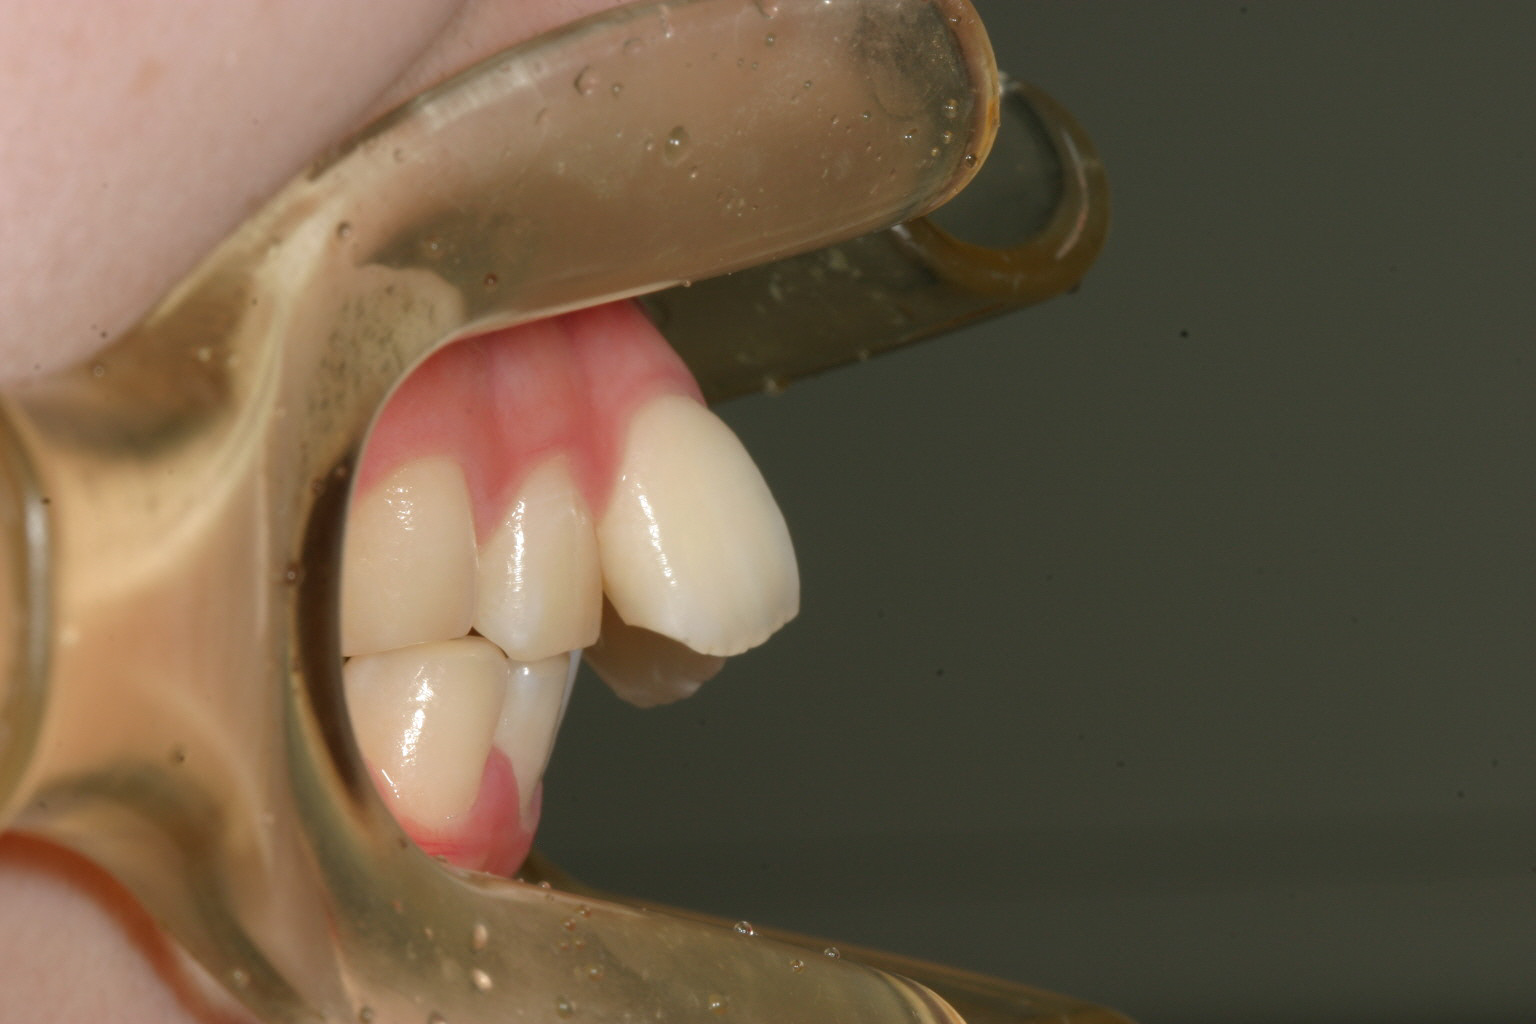

側面観もかなり飛び出してます。

飛び出しも無くなりました。